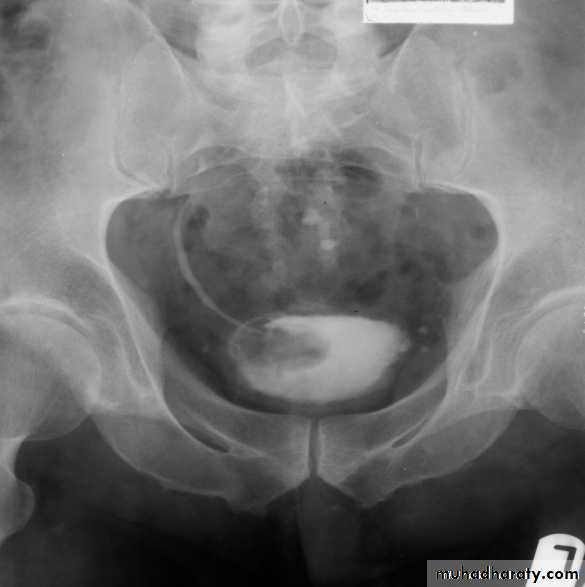

*Calcification is very common and important diagnostic findings. Very common in bladder ,less frequent in lower ureters ,but in advanced case involve the whole length of ureter .

*The appearance depends on degree of fullness of bladder ; thin linear opacity outlining bladder wall.

Empty bladder shows crowded linear opacities with calcified plaques.